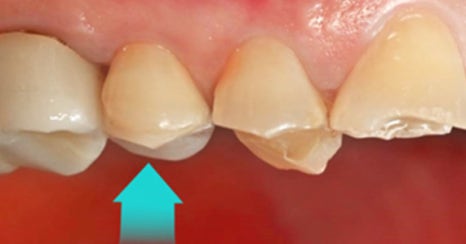

하루네이트는 바쁜 일상에서도

자신 있는 미소를 완성할 수 있는

하루플란트치과의 당일 라미네이트 치료입니다.

특히 물리적 거리상 여러 번 내원하기 어려운 분

또는 불편한 임시 치아를

피하고 싶은 분께 이상적입니다.

하루네이트의 당일 제작은 전문적인 기술과

첨단 장비를 갖춘 자체 기공소에서 이루어집니다.

숙련된 기공사의 세심한 작업과

지루하게게 발생하는 대기 시간을

최소화하기 위한 배려가 결합되어,

환자에게 최상의 결과를 제공합니다.